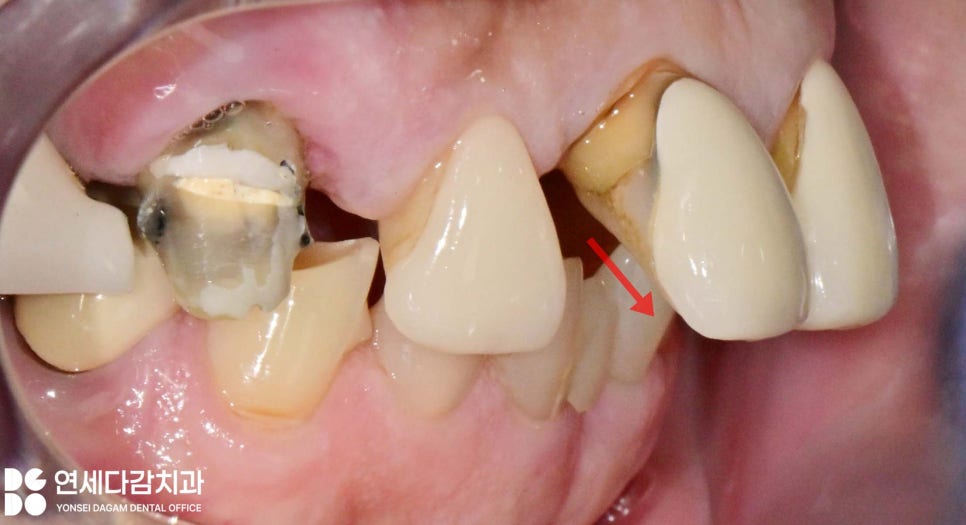

치주염이 심해지면 치아가

움직이기 시작하여 치아 사이에

공간이 생기기도 하고,

특히

위 앞니는 앞으로 뻐드러진 형태로

변하기도 합니다.

이런 현상이 생기는 이유는

치주염으로 인해 치아 주변의

잇몸뼈가 흡수되면서

단단히 지지해 주던 잇몸뼈와

치주 인대가 약해지기 때문입니다.

이 상태에서 교합이 불안정해지고,

혀의 압력에 의해 앞니가

앞으로 밀려나오게 됩니다.

앞니 부위를 전치부라고 하는데,

전치부는 심미적으로

중요한 역할을 하기 때문에

기능적인 면뿐만 아니라 심미적인 요소도

중요하게 고려해야 됩니다.

보존적인 접근 방법

오금동 치과 에서 보여드린

상황에서도 동요도가 심하지 않다면

발치하지 않고

가능한 한 보존하는 방향으로

치료 계획을 세우는 것을 목표로 합니다.

따라서 여러 개의 크라운을 서로

스플린트(splint) 하는 방법을

이용하게 됩니다.

하나의 보철로 여러 개의

치아를 씌우는 방식을 말하며,

오금동 치과 에서는 이 방법을 통해

흔들리는 치아들을 묶어 움직임이 제한돼

고정력을 증가시켜 주는 것이죠.

또한 개별 치아가 받을 힘이

여러 치아로 분산되어 부담을

줄일 수 있습니다.